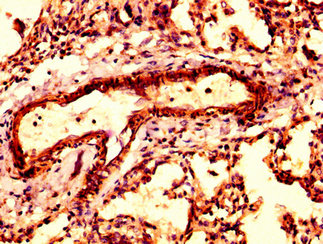

IHC image of CSB-PA002130LA01HU diluted at 1:300 and staining in paraffin-embedded human lung tissue performed on a Leica BondTM system. After dewaxing and hydration, antigen retrieval was mediated by high pressure in a citrate buffer (pH 6.0). Section was blocked with 10% normal goat serum 30min at RT. Then primary antibody (1% BSA) was incubated at 4°C overnight. The primary is detected by a biotinylated secondary antibody and visualized using an HRP conjugated SP system.